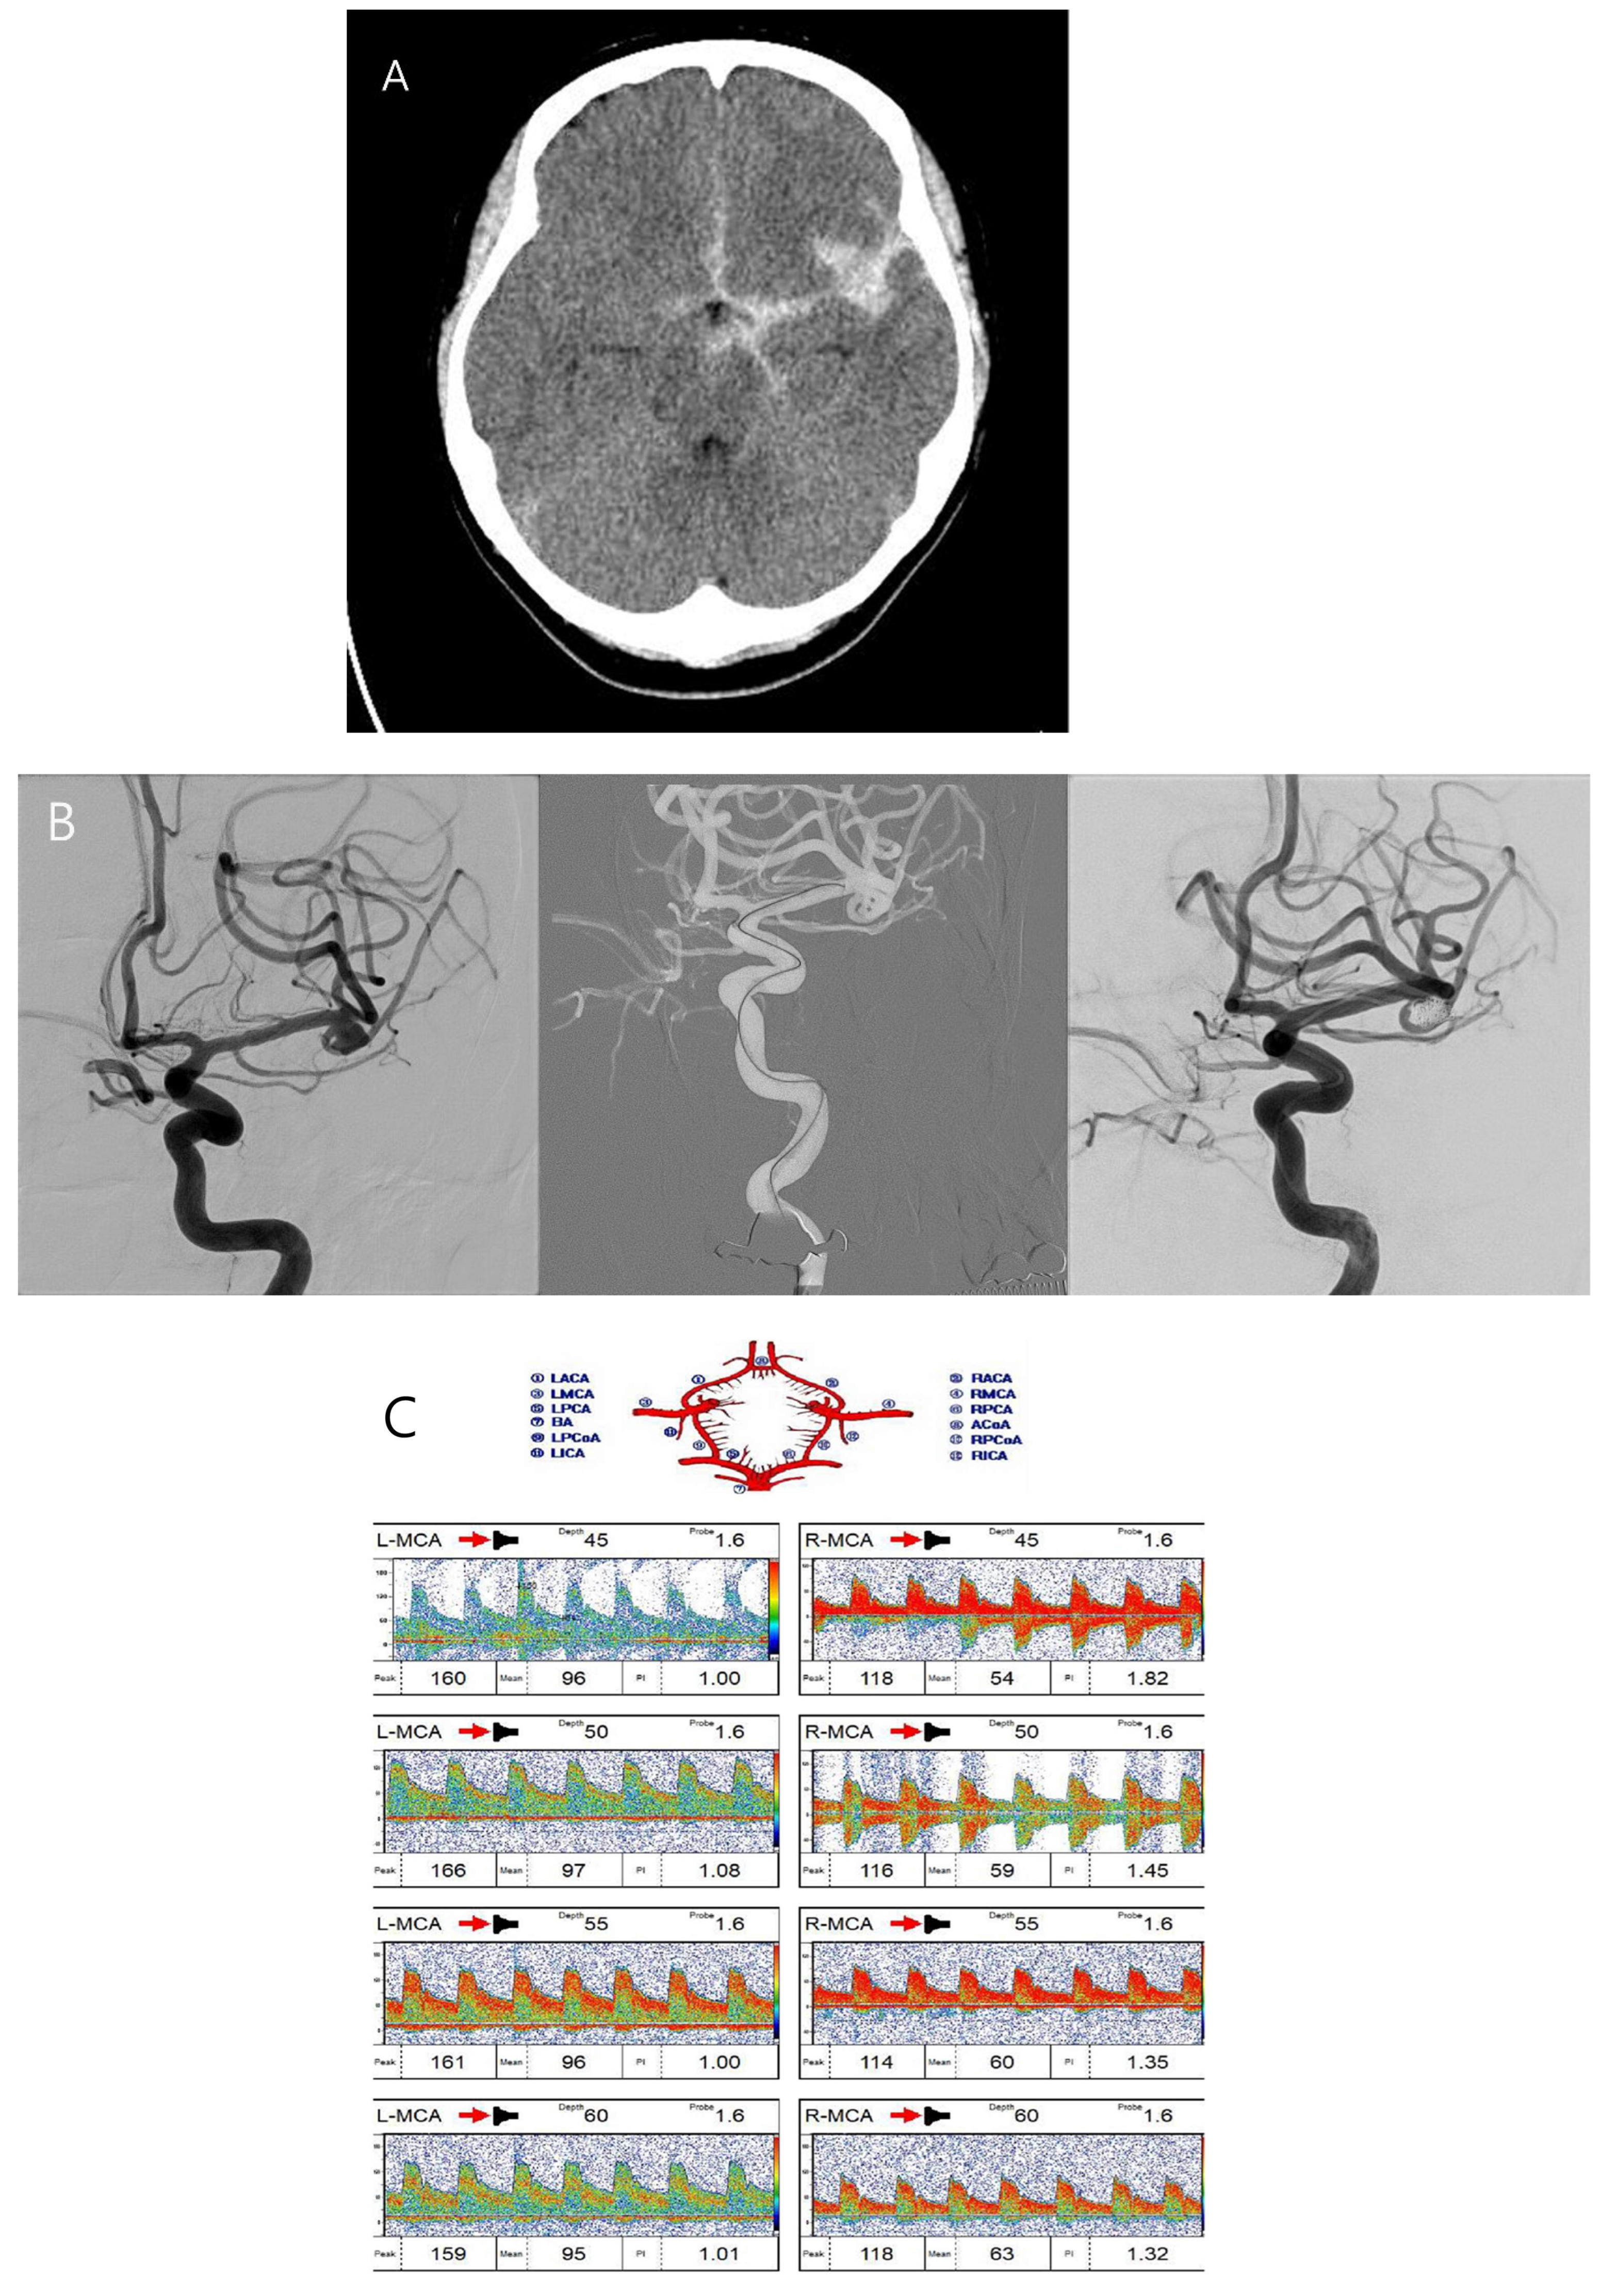

A fifty-year-old female patient with a severe headache visited our emergency room. She had hypertension and had been taking a calcium channel blocker. Initial brain CT and CT angiography revealed an aneurysmal subarachnoid hemorrhage (Hunt–Hess grade 2 and modified Fisher grade 3) due to a ruptured left MCA bifurcation aneurysm (Figure 3A). An emergent TFCA was performed, revealing the aneurysm to have a maximal size of 6.21 mm and a neck size of 3.21 mm. Emergent coil embolization using the double microcatheter technique was successfully performed. The ruptured aneurysm occluded completely without procedural complications (Figure 3B). We inserted a lumbar drain to treat mild hydrocephalus, and the patient was admitted to the ICU for intracranial pressure control and vasospasm prevention. Initial TCD ultrasonography was conducted the day after coil embolization (Figure 3C,D). TCD ultrasonography monitoring continued for 2 weeks to detect vasospasm. The blood flow velocity of the left MCA was increased slowly. However, the patient experienced no clinical symptoms except for a headache. Seven days after coil embolization, she complained of severe headache and left-side visual disturbance. Immediate follow-up TCD ultrasonography revealed severe vasospasm, the mean blood flow velocity having doubled (Figure 3E,F). TFCA was conducted to confirm and treat the vasospasm. TFCA revealed severe vasospasm in the cerebral vessels of the left hemisphere (Figure 3G: the white arrow and circle denote regions of decreased blood flow attributable to vasospasm). Intra-arterial nimodipine angioplasty was performed for 4 days, after which the vasospasm and her symptoms gradually improved (Figure 3H–J: the white arrow and circle highlight areas of restored blood flow following intra-arterial nimodipine angioplasty). She was discharged at 3 weeks after coil embolization without neurologic symptoms. Her mRS score at 6 months post-embolization was 0.

Figure 3.

Case illustration of patient who suffered subarachnoid hemorrhage.